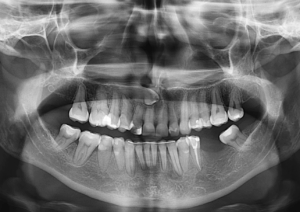

Por lo cual se diseñó un estudio transversal con 74 contactos de 28 imágenes CBCT existentes de niños de entre 3 y 14 años, obtenidos de la Academia de Educación Dental de la India, Chennai, India. La forma del área de contacto se observó en tres niveles, los tercios coronal, medio y apical, en tres secciones diferentes de CBCT. La prevalencia de los tipos de áreas de contacto se expresó en forma de números y porcentajes. Los resultados mostraron cuatro tipos diferentes de áreas de contacto entre los molares primarios, a saber, tipo O, tipo X, tipo I y tipo S, según las formas observadas; Por lo tanto, la clasificación propuesta se conoce como OXIS. El patrón más común observado fue I (66.2%), seguido de X (21.6%), O (9.4%) y el menos común fue S (2.7%). (Figura 1 y Figura 2)

Llegando a la conclusión que la evaluación tridimensional de las áreas intactas de contacto interproximal entre los molares primarios es de cuatro tipos, O, X, I y S.